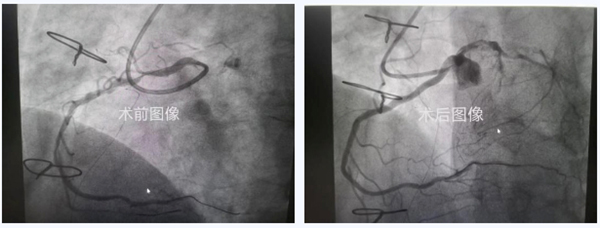

造影显示:右冠开口于左窦上方,巨大的右冠弥漫性狭窄伴重度钙化。多种指引导管均未能到位,最后,王健主任通过多种器械融合技术终于使指引导管和冠脉同轴。

右冠开口异常患者的介入治疗

经过长达2小时的手术,成功解除了冠脉狭窄。经过短期心脏康复,王大爷心绞痛症状完全缓解,恢复正常的生活状态。